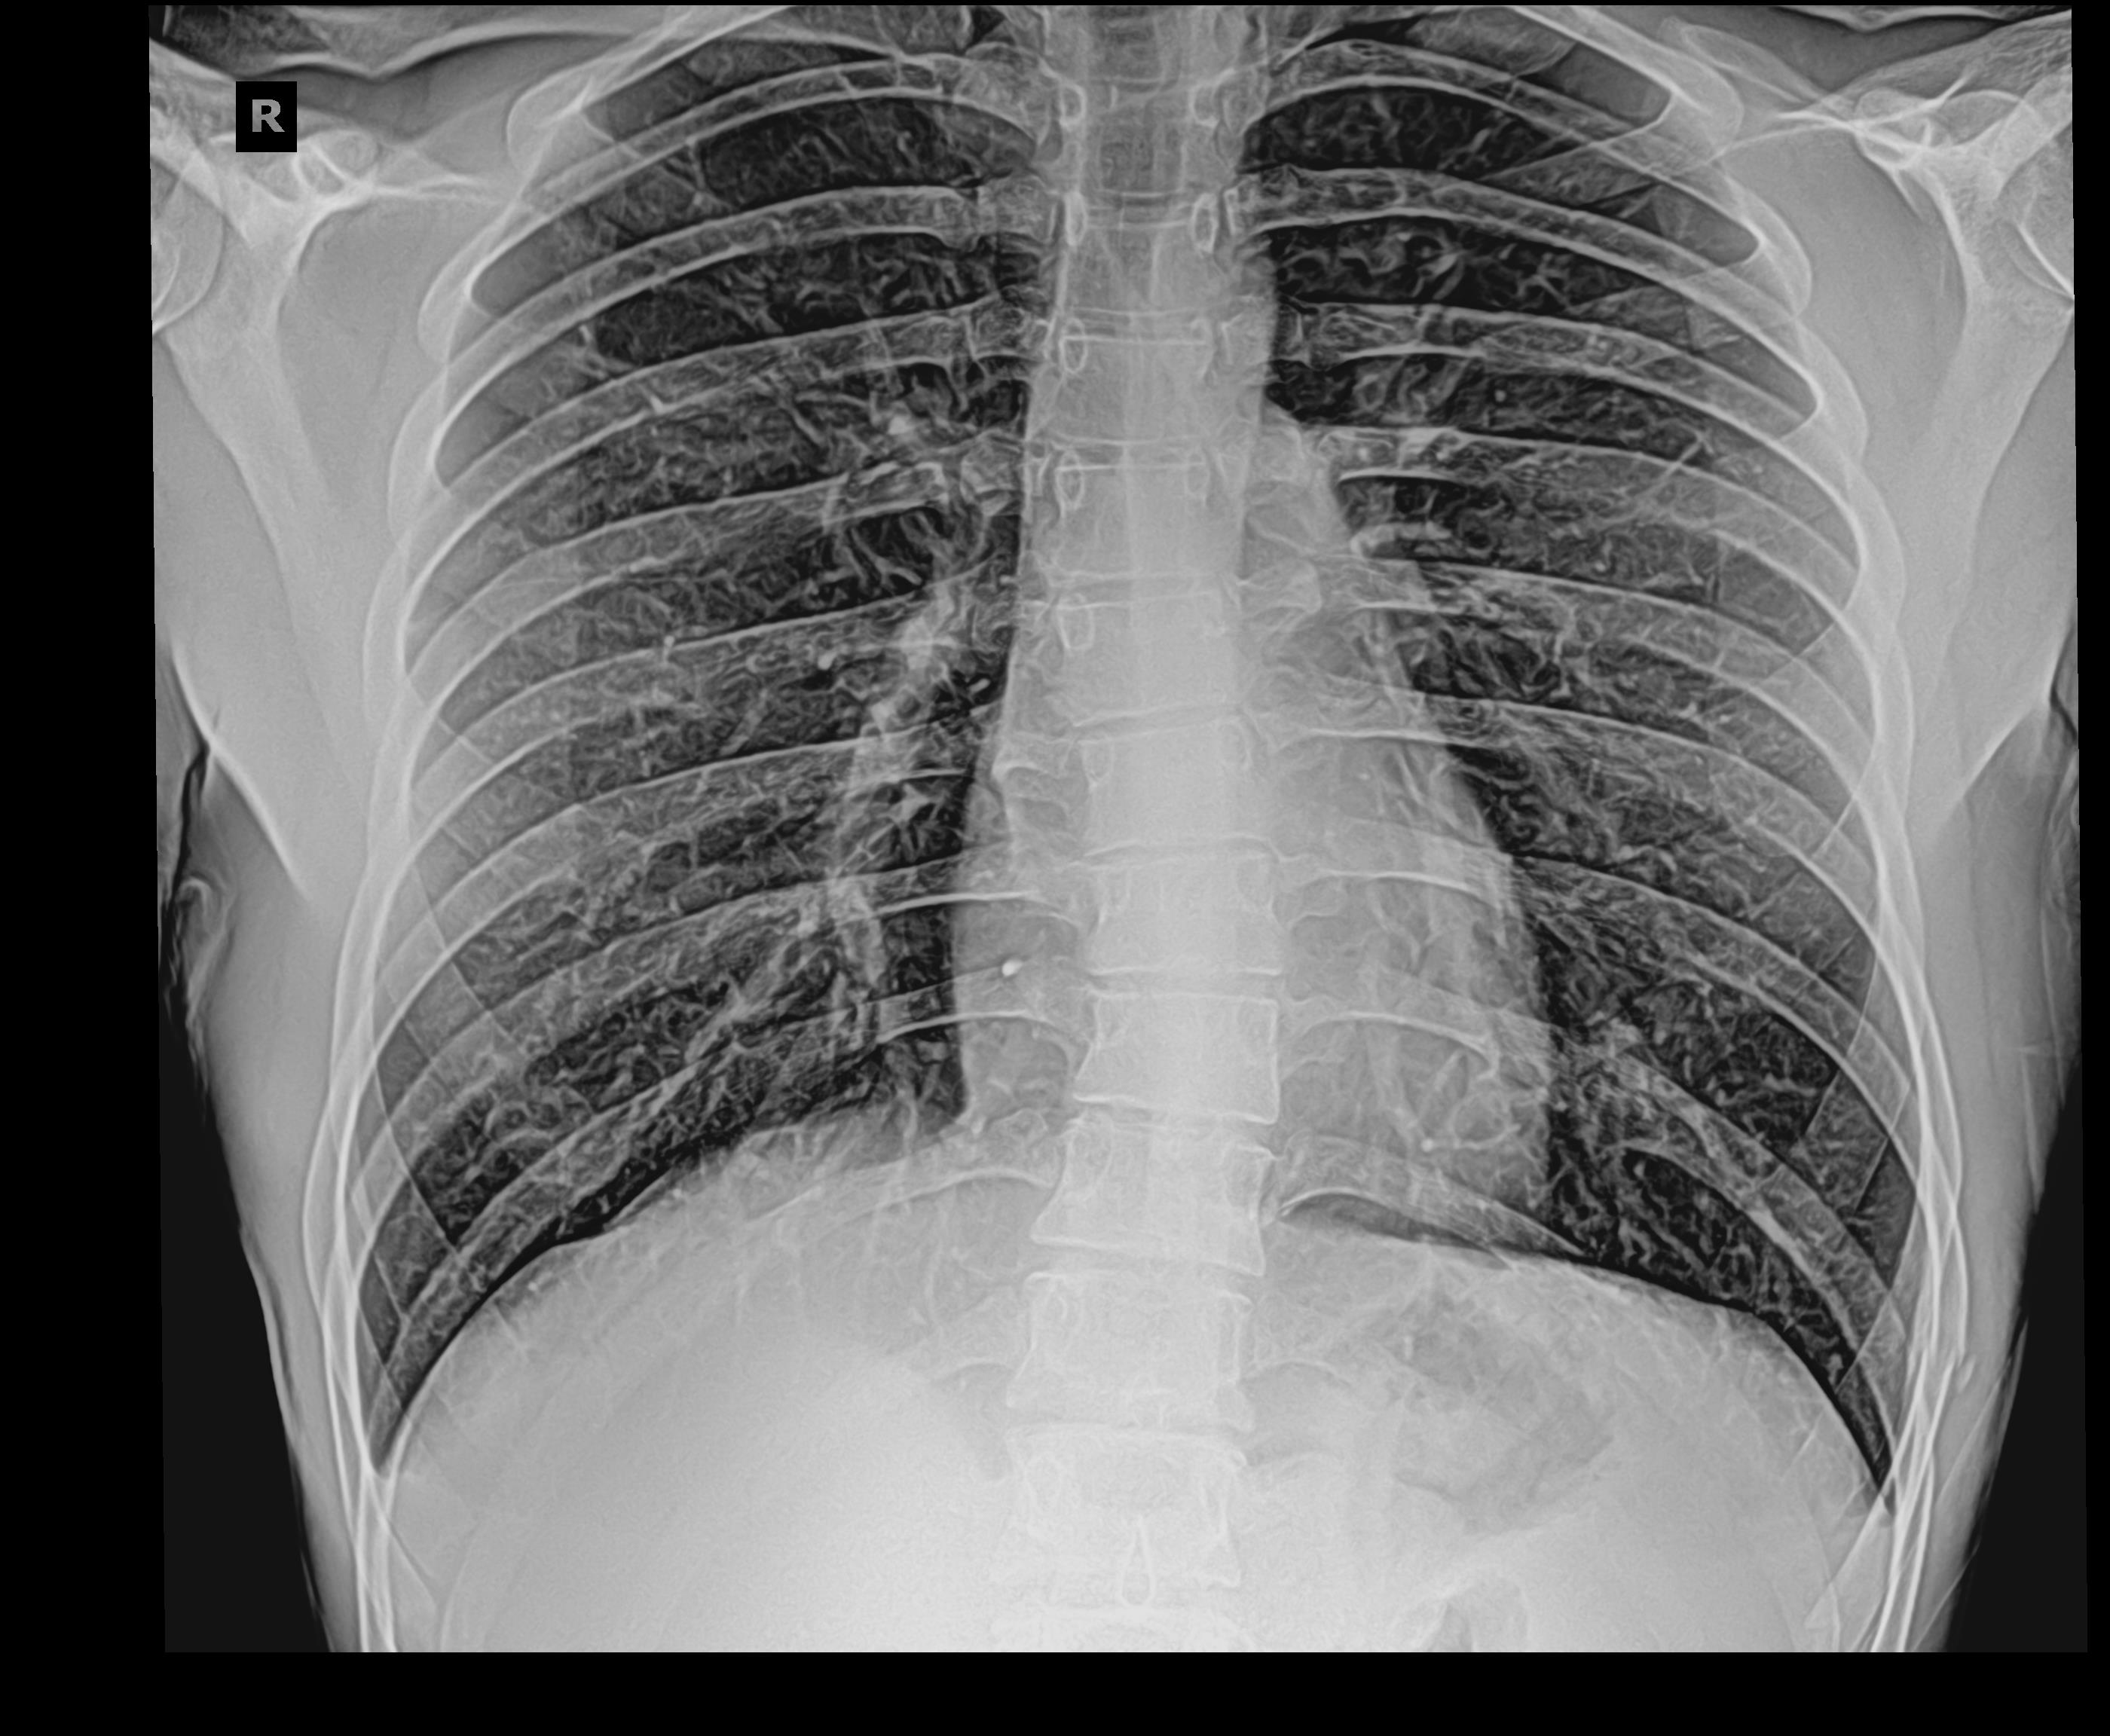

Снимок грудной клетки здорового ребенка: примеры и диагностика